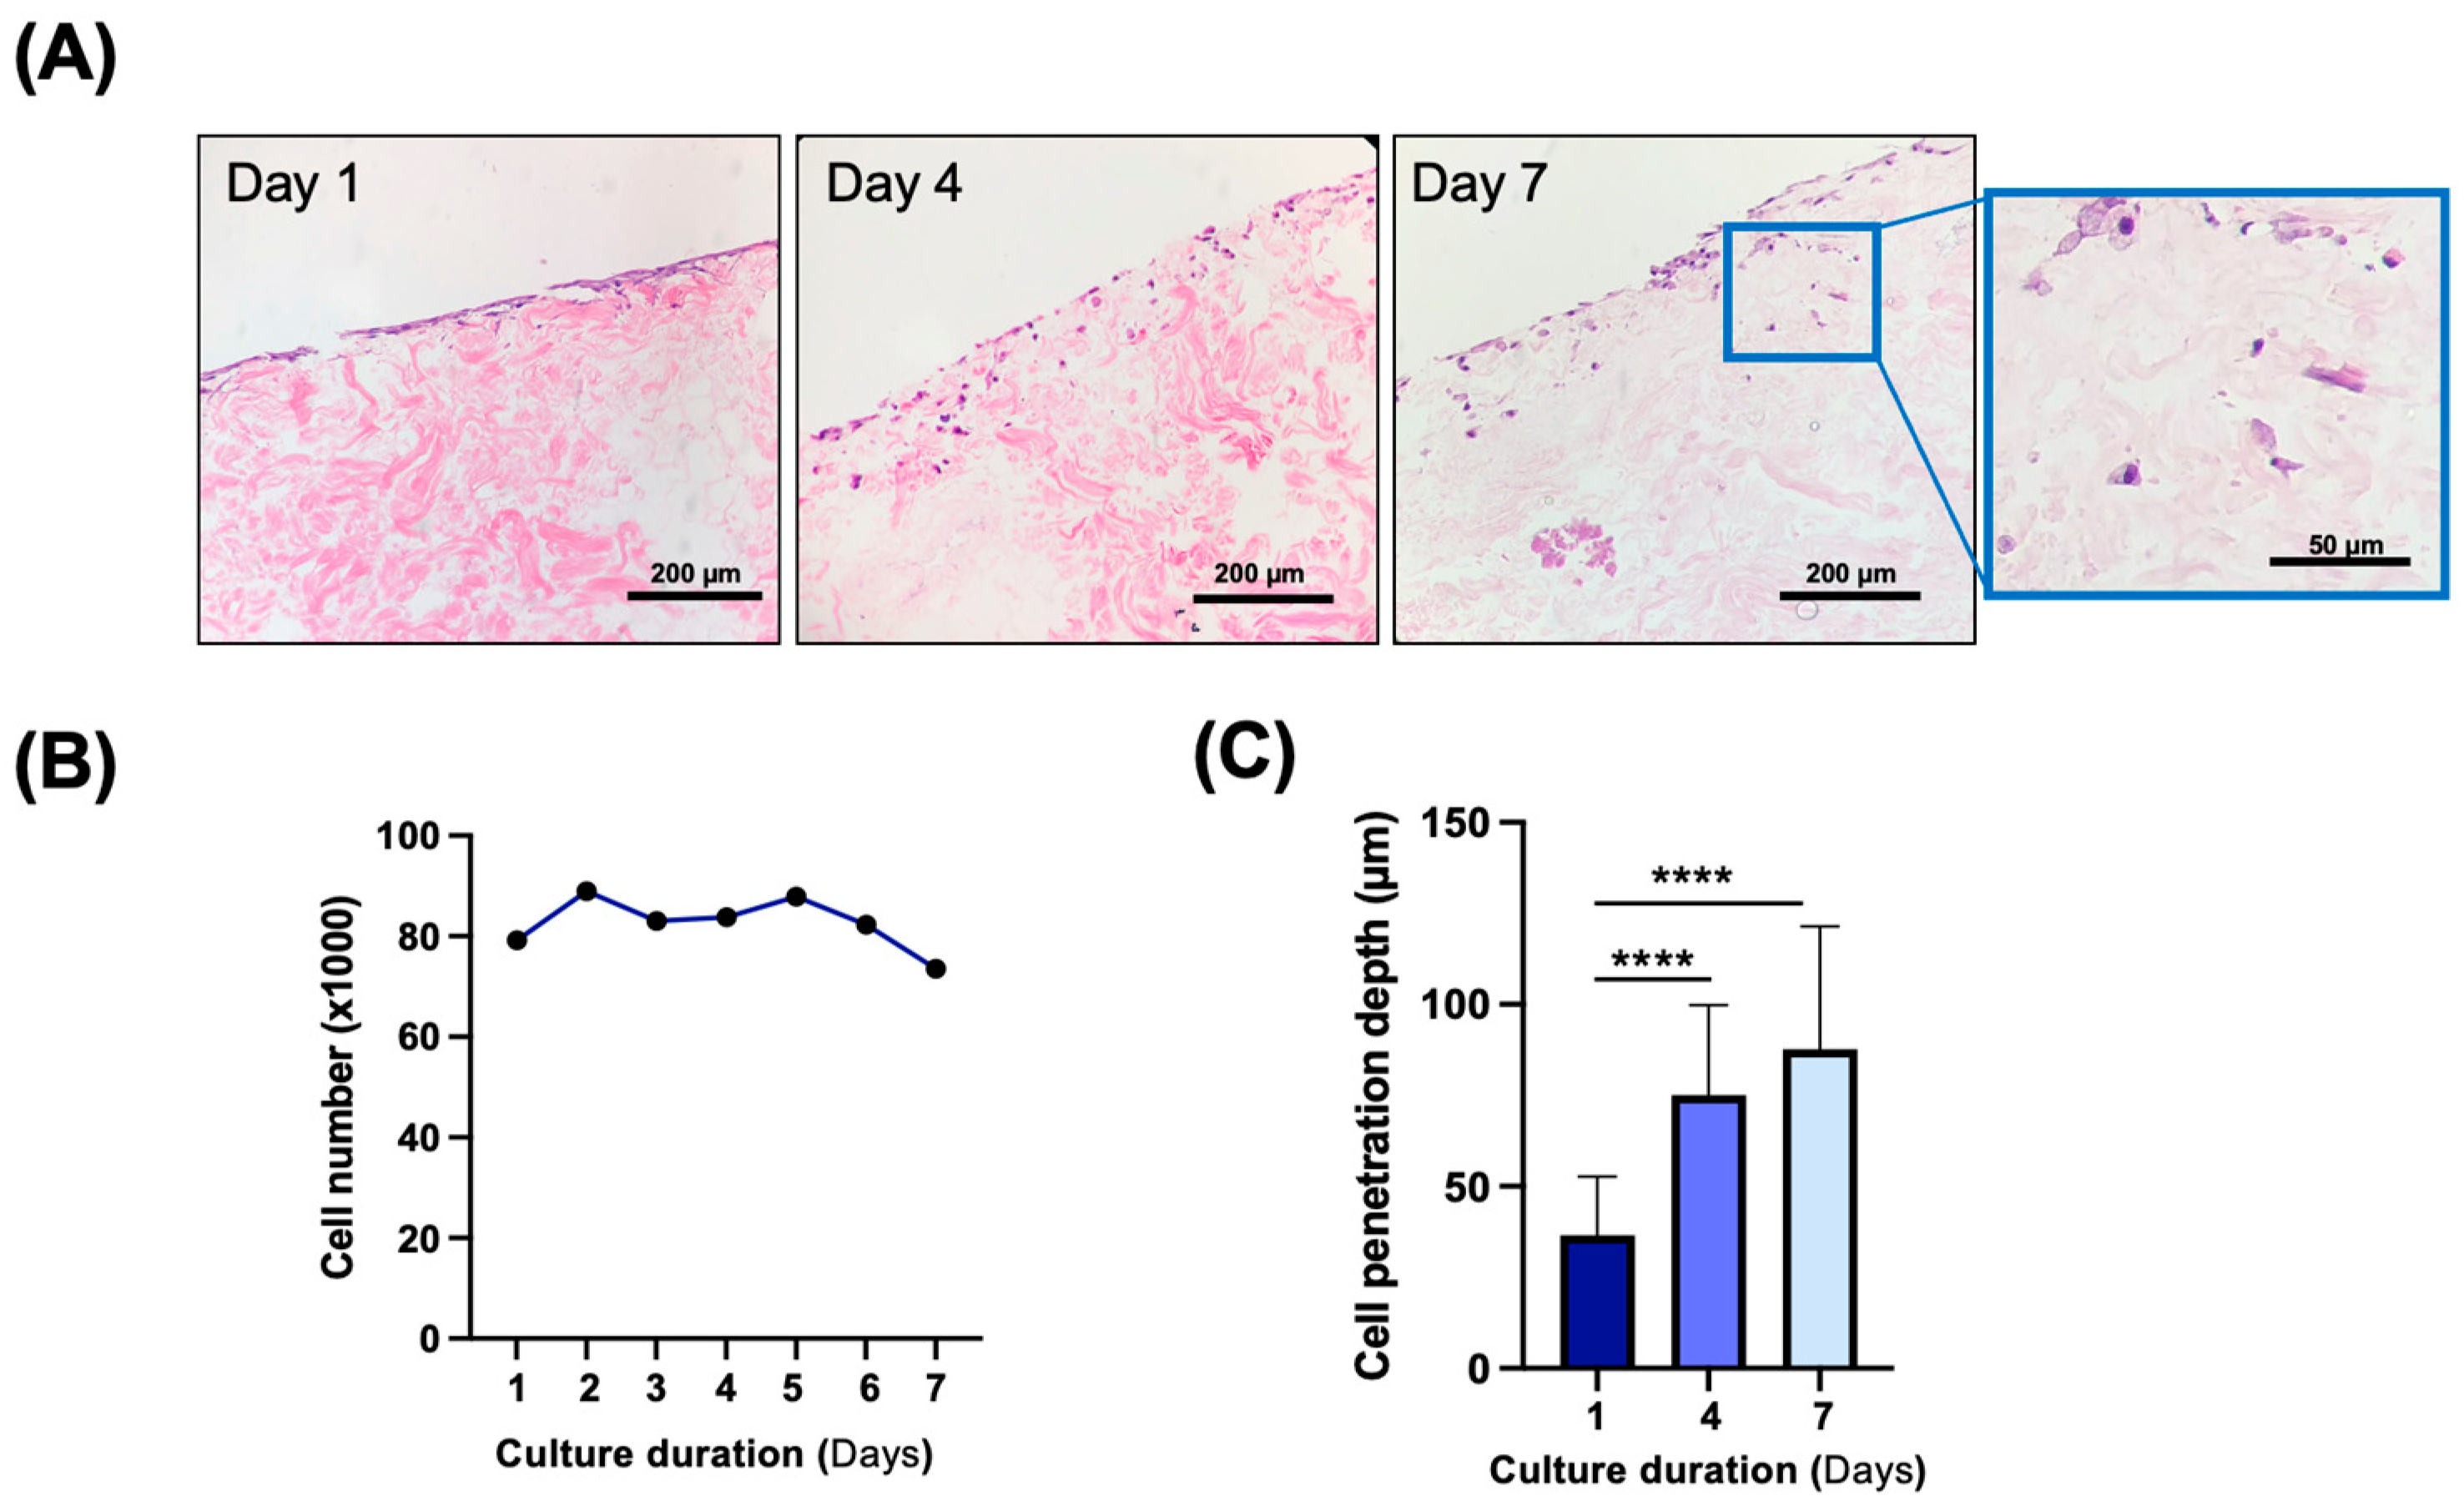

3.4. In Vitro and In Vivo Biocompatibility of Decellularized Facial Grafts